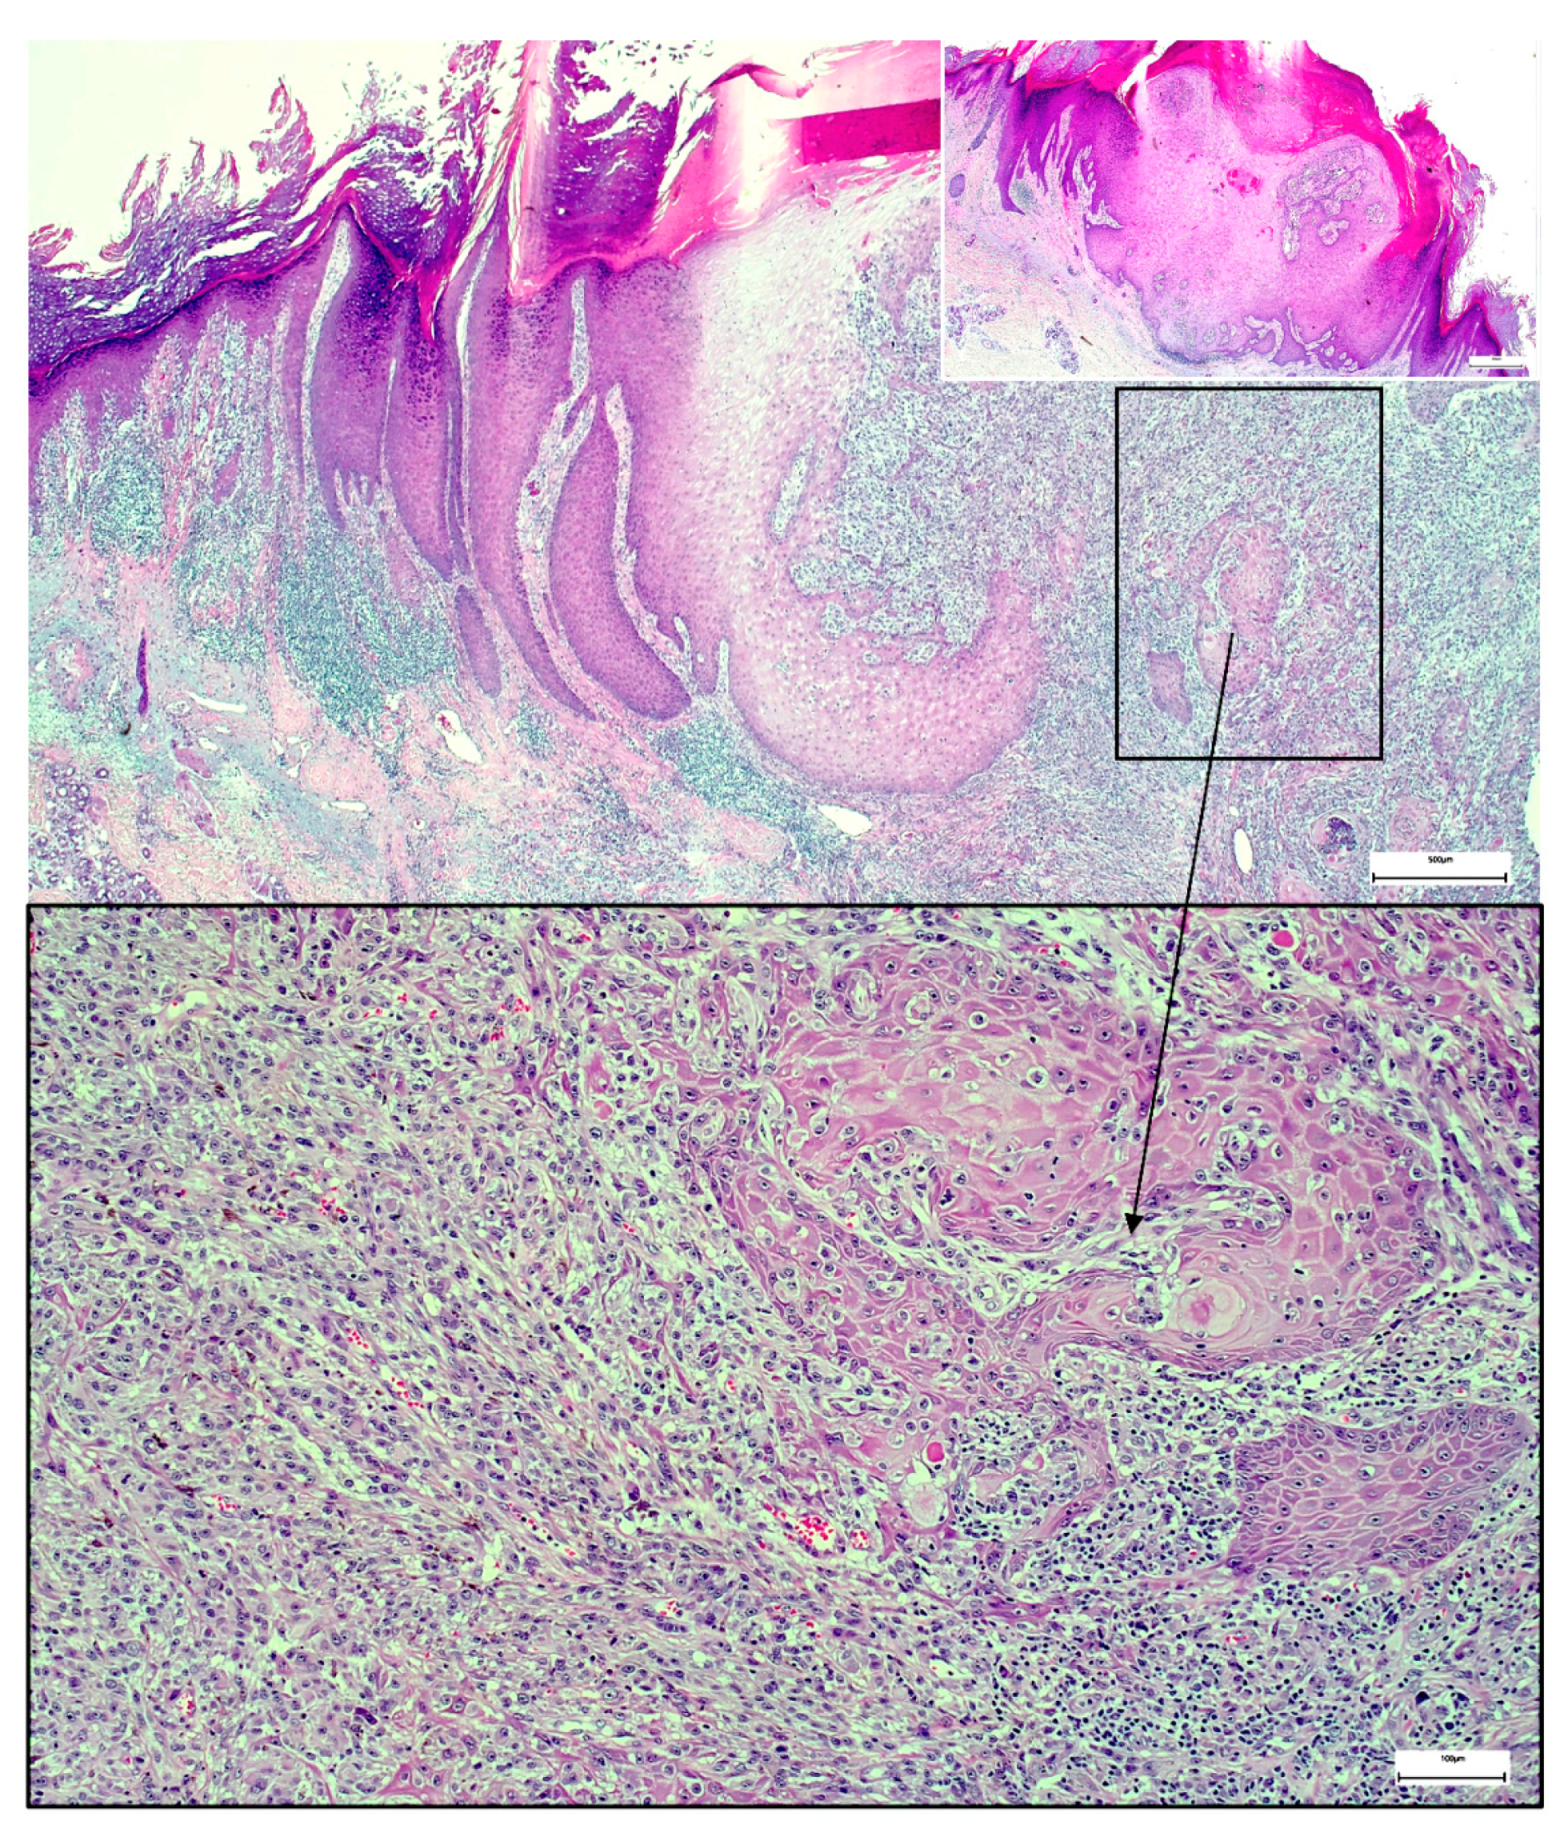

A Wolf in Sheep’s Clothing: Collision of Melanoma and Keratoacanthoma

:1. Case Presentation